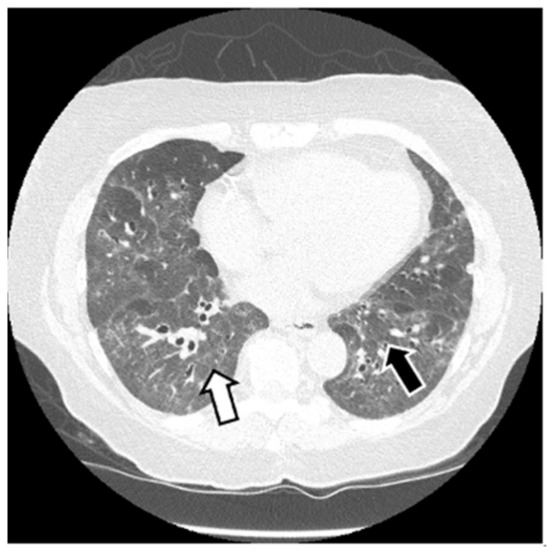

6.2. Histopathologic and Radiographic Findings in Myositis-Associated ILD